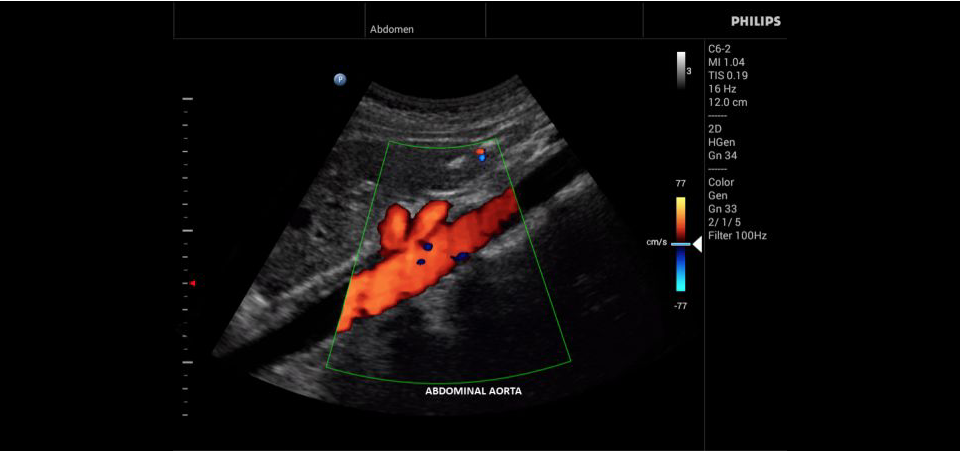

• Исследования сосудов;

• Цветное допплеровское картирование

• Конвексный УЗИ датчик Philips С6-2